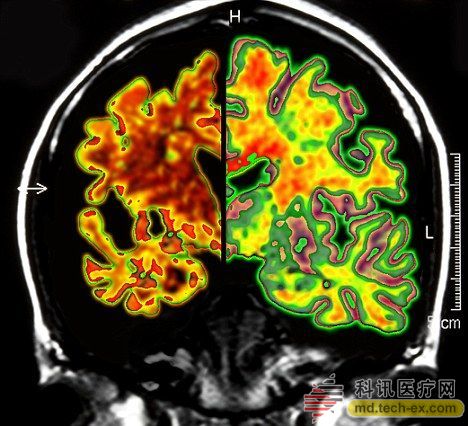

在手術中,所有病患的腦部將被植入電極,這些電極與一個類似起搏器的裝置相連接,能夠每秒鐘發(fā)出130次電脈沖。羅森博格表示,病人并不會感受到電脈沖的存在。 研究人員表示,所有接受臨床試驗的病人同時都會被植入這個“起搏器”裝置。其中,一半病人的“起搏器”將于手術后兩周開啟,而另一半病人的要在手術后一年才會開啟。目前,參加臨床試驗的病人和醫(yī)生并不知道分組情況。 其實早在2010年,加拿大就已經對這種大腦“起搏器”展開臨床試驗。當時,有6名輕微老年癡呆癥患者參加。當時的試驗結果顯示,在13個月的觀察期中,這些病患的葡糖糖代謝速度持續(xù)上升,這也就說明他們的大腦神經元正在工作。而在同時期內,大部分老年癡呆癥患者的葡萄糖代謝水平則是在不斷下降。